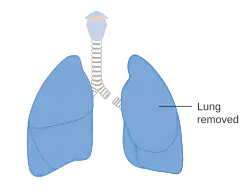

A pneumonectomy (or pneumectomy) is a surgical procedure to remove a lung. It was first successfully performed in 1933 by Dr. Evarts Graham. This is not to be confused with a lobectomy or segmentectomy, which only removes one part of the lung.

There are two types of pneumonectomy: simple and extrapleural. A simple pneumonectomy removes just the lung. An extrapleural pneumonectomy also takes away part of the diaphragm, the parietal pleura, and the pericardium on that side.[1]

Anatomical changes

After a pneumonectomy is performed, changes in the thoracic cavity occur to compensate for the altered anatomy. The remaining lung hyperinflates as well as shifting over along with the heart towards the now empty space. This space is full of air initially after surgery, but then it is absorbed, and fluid eventually takes its place.[9] The fluid which fills the residual space in the chest cavity slowly gelatinizes into a proteinaceous material, and the chest scaffold collapses slightly.

Living with one lung

As with the kidneys, it is often possible for a person to live with just one lung. Although it is not possible for the lung to re-grow like the liver, the body is able to compensate for the reduced lung capacity by slow and gradual expansion of the other remaining lung. Post-pneumonectomy patients in due time reach about 70–80 percent of their pre-surgery lung function.[10] People have been able to return to near-normal lives, including running marathons after a pneumonectomy, provided there has been adequate cardio-pulmonary conditioning.[11]